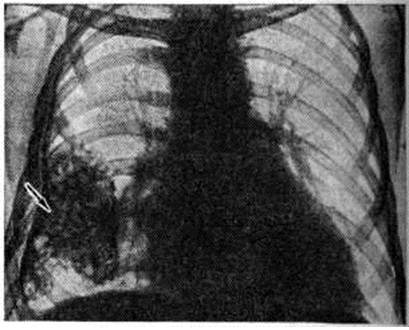

Выпотной Плеврит с накоплением серозного и серозно-фибринозного выпота является самым частым вариантом туберкулёзного Плеврит Наблюдается при образовании множественных туберкулёзных бугорков на плевре, иногда сливающихся между собой в более крупные очаги, а также при казеозном некрозе отдельных крупных очагов. Однако в этом случае в клеточном составе выпота преобладают нейтрофилы. При более распространённом казеозном некрозе плевры выпот становится серозно-гнойным, а при обширных поражениях — гнойным. В случае прорыва в плевральную полость субплеврально расположенных туберкулёзных очагов и каверн возникает обширный казеозный некроз плевры, сопровождающийся также экссудативной воспалительной реакцией плевры и накоплением выпота, нередко гнойного. При гнойном Плеврит (эмпиеме плевры) гнойный выпот скапливается преимущественно в нижних отделах плевральной полости. Гнойный Плеврит пневмококковой природы обычно сочетается с фибринозным выпотом и поэтому характеризуется скоплением гноя среди фибринозных «камер», располагающихся в нижних отделах плевральной полости. Стафилококки и стрептококки вызывают чисто гнойный Плеврит со скоплением жёлто-зелёного сливкообразного гноя в первом случае и жидкого серого — во втором. Плевра при этом тусклая, покрыта гноем, иногда некротизирована, пронизана колониями микробов. Мезотелий слущен, все слои плевры инфильтрированы нейтрофильными гранулоцитами, макрофагами, границы слоёв стёрты. При наличии в плевре тромбоваскулитов гнойная инфильтрация с висцеральной плевры может распространяться на лёгкое — так называемый кортикоплеврит, а с париетальной — на межмышечную клетчатку грудной стенки. Гнилостный Плеврит является следствием проникновения в плевру гнилостных микробов из очагов гангренозного распада лёгкого, осложнившего пневмонию, инфаркт или рак лёгкого. Выпот при этом буровато-серый с гнилостным запахом, иногда процесс течёт с образованием газа. При неэффективном лечении эмпиема приобретает хронический течение: грануляции рубцуются, лимфатических, коллекторы плевры облитерируются, развивается сетчатый лимфогенный пневмосклероз (смотри полный свод знаний). При этом спавшееся лёгкое фиксируется, фибринозные наложения на его поверхности, а также на париетальной плевре подвергаются организации; в результате этого создаётся ригидная остаточная плевральная полость, в которой сохраняется гнойный процесс, приобретающий хронический характер, формируются бронхоплевральные и плевро-кожные свищи. На фоне формирования спаек, свободный выпот в плевральной полости осумковывается, сгущается, иногда превращаясь в крошковатую массу, содержащую кристаллы холестерина (псевдохилёзный Плеврит) и известь. Иногда при обширной гнойной деструкции лёгочной ткани висцеральная плевра пронизана множеством бронхиальных свищей (смотри полный свод знаний), так называемый «решетчатое лёгкое». Функциональные нарушения, возникающие при плевритеФункциональные нарушения, возникающие при плеврите. Болевая реакция, возникающая при сухом Плеврит в результате трения воспалённых и покрытых фибринозными наложениями частей висцеральной и париетальной плевры и раздражения рецепторов, которыми обильно снабжена париетальная плевра, ведёт к ограничению глубины и, соответственно, увеличению частоты дыхания (смотри полный свод знаний). При накоплении выпота возникают нарушения, связанные с коллабированием и компрессионным ателектазом лёгкого, а также смещением средостения в здоровую сторону. При умеренном количестве выпота возникает ограничение лёгочной вентиляции (смотри полный свод знаний), а компрессионный коллапс части альвеол может способствовать возникновению умеренной гипоксемии за счёт изменения соотношения между лёгочной вентиляцией и кровотоком. Смещение средостения при большом количестве выпота ведёт к ограничению вентиляции второго лёгкого, нарастанию дыхательной недостаточности (смотри полный свод знаний) и расстройству кровообращения (смотри полный свод знаний) в результате смещения сердца, нарушения притока к нему крови вследствие общего повышения внутригрудного давления, перегиба полых вен, что может привести к гибели больного. При гнойном Плеврит интоксикация, обусловленная всасыванием обширной поверхностью плевры микробных токсинов и продуктов распада белка (гнойно-резорбтивная лихорадка по И. В. Давыдовскому, 1954), ведёт к истощению больного, массивной потере белка (гнойно-резорбтивное истощение), изменениям со стороны паренхиматозных органов, в первую очередь почек — токсический нефрит, амилоидоз (смотри полный свод знаний Гнойно-резорбтивная лихорадка). Клиническая картинаКлиническая картина при Плеврит складывается из проявлений основного заболевания, осложнившегося Плеврит, проявлений собственно Плеврит, а также расстройств со стороны жизненно важных органов и систем, вызываемых Плеврит В клинике Плеврит различного происхождения выделяют синдром сухого (фибринозного) Плеврит, синдром выпотного негнойного Плеврит и синдром гнойного Плеврит (эмпиема плевры). В динамике заболевания эти синдромы могут наблюдаться изолированно или же переходить один в другой. Сухой плеврит является выражением реакции плевры на неспецифический воспалительный процесс в лёгочной паренхиме (пневмонию, абсцесс лёгкого), и его клинические, проявления обычно дополняют симптоматику этих заболеваний. В других случаях сухой Плеврит развивается как бы изолированно, без отчётливых изменений в лёгком, например, в результате переохлаждения. В этих случаях причиной возникновения фибринозного Плеврит может являться реакция плевры, сенсибилизированной к туберкулёзному антигену, который выделяется из очагов инфекции, локализующихся в бронхолёгочных лимфатических, узлах или в лёгочной ткани и клинически не проявляющихся. Сухой Плеврит обычно протекает остро или подостро. Основной жалобой больных является острая боль в соответствующей половине грудной клетки, связанная с дыханием. Боль локализуется в зоне появления фибринозных наложений и наиболее интенсивна в задненижних отделах грудной клетки, где взаимная подвижность висцеральной и париетальной плевры максимальна. Боль усиливается при глубоком вдохе, а также при наклоне туловища в противоположную сторону (симптом Шепельманна). Для уменьшения болевых ощущений больные стремятся дышать поверхностно или же принимают вынужденное положение в постели на больном боку, иммобилизируя таким образом поражённую половину грудной клетки. Общее состояние больных обычно остаётся удовлетворительным, если сухой Плеврит не сопутствует тяжёлым изменениям в лёгких. Температура достигает субфебрильных цифр. Дыхание поверхностное, учащённое, экскурсии грудной клетки уменьшены на стороне поражения. При пальпации грудной стенки на больной стороне, особенно у худощавых больных, можно определить характерную крепитацию, связанную с дыханием. При верхушечных Плеврит иногда выявляется умеренная болезненность трапециевидных мышц (симптом Штернберга) и мышц груди (симптом Поттенджера); может возникнуть триада Горнера (анофтальм, псевдоптоз, миоз) вследствие вовлечения в воспалительный и рубцовый процесс веточек шейно-симпатического сплетения (смотри полный свод знаний Бернара — Горнера синдром); при поражении плечевого сплетения могут появиться признаки плексита (смотри полный свод знаний). При парамедиастинальной локализации Плеврит и развитии слипчивого медиастинита (смотри, полный свод знаний) возможно вовлечение в спаечный процесс ветвей блуждающего нерва, что ведёт к возникновению сердцебиений, иногда к нарушению моторной и секреторной функции желудка. Главным и в большинстве случаев единственным аускультативным симптомом сухого Плеврит является шум трения плевры над областью фибринозных наложений. Иногда шум трения плевры бывает слышен даже на расстоянии (симптом Щукарёва). При исследовании крови может наблюдаться ускорение РОЭ и небольшой лейкоцитоз. Диагностические трудности могут встретиться при диафрагмальных сухих Плеврит, которые нередко сопровождают базальные пневмонии или же воспалительные процессы в органах верхнего этажа брюшной полости (в поддиафрагмальном пространстве). Шум трения плевры при этом обычно отсутствует, болевые ощущения могут иррадиировать по диафрагмальному нерву вверх, в область шеи, а по нижним межрёберным нервам в область живота, при этом нередко выявляется ригидность мышц живота на стороне поражения. Иногда возникает болезненная икота, боль при глотании. При пальпации могут выявляться болезненные точки между ножками грудино-ключично-сосцевидной мышцы (признак Мюсси), в первых межрёберных промежутках у грудины, по линии прикрепления диафрагмы к рёбрам, в области остистых отростков верхних шейных позвонков. При аускультации в нижних долях лёгких иногда выслушиваются хрипы, характерные для базальной пневмонии, а рентгенологически обнаруживается инфильтрация в базальных сегментах нижней доли. В ряде случаев при диафрагмальных Плеврит ошибочно ставится диагноз острого заболевания органов верхнего этажа брюшной полости и даже осуществляется необоснованная лапаротомия. Течение «изолированного» сухого Плеврит обычно непродолжительно. Через несколько дней боли стихают, общее состояние нормализуется, через 2—3 недели больной выздоравливает. Сухой Плеврит может переходить в выпотной. Выпотной негнойный плеврит чаще развивается остро. Начальные проявления и клинические, картина его разнообразны. В случаях, когда появлению жидкого выпота предшествовал сухой Плеврит, болевые ощущения на стороне поражения уменьшаются или исчезают вовсе, сменяясь чувством тяжести, переполнения, постепенно нарастающей одышкой, прогрессированием слабости, утомляемости. В подострых случаях указанные симптомы возникают исподволь, незаметно, иногда после периода общего недомогания и небольшого повышения температуры. Отмечается сухой кашель рефлекторного характера. При значительном накоплении выпота появляется чувство нехватки воздуха в покое. Больные стремятся принять в постели вынужденное положение с приподнятой верхней частью туловища, причём лежат преимущественно на больном боку, что обеспечивает меньшее давление выпота на средостение и меньшее смещение последнего. При осмотре отмечается цианоз кожных покровов и видимых слизистых оболочек, набухание шейных вен. Дыхательные экскурсии на стороне поражения бывают уменьшены, а у худощавых больных со слабо развитой мускулатурой и, в особенности, у детей иногда заметно выбухание межрёберных промежутков. При значительных выпотах поражённая половина грудной клетки увеличивается в объёме. Кожа в нижней части грудной клетки становится отёчной, а кожная складка, приподнимаемая между двумя пальцами, представляется более массивной, чем с противоположной стороны (симптом Винтриха). Пульс, как правило, учащён. Перкуторно границы тупости сердца и средостения смещены в здоровую сторону. На стороне поражения сердечная тупость сливается с притуплением , обусловленным плевральным выпотом. Основным симптомом выпотного Плеврит является обширное притупление перкуторного звука преимущественно в нижних отделах грудной клетки, где при отсутствии сращений независимо от места образования скапливается выпот. Свободный плевральный выпот определяется перкуторно, если его количество превышает 300—400 миллилитров. По данным И. И. Йонкова и С. Т. Тодорова (1966), при уровне притупления на IV ребре по среднеключичной линии в плевральной полости взрослого больного содержится 1 —1,5 литров жидкости, а повышение уровня притупления на одно ребро соответствует увеличению объёма жидкости примерно на 0,5 литров. Верхняя граница притупления зависит от количества жидкости и имеет дугообразную форму, максимально возвышаясь по задней подмышечной линии (линия Эллиса—Дамуазо—Соколова). Однако эта линия не соответствует, как полагали раньше, верхней границе выпота. Последняя, по данным Дейвиса (S. Davis, 1963), обычно является горизонтальной. Это несоответствие объясняется тем, что верхняя граница притупления идёт по уровню, на котором слой выпота имеет толщину, достаточную для того, чтобы вызвать изменение перкуторного звука. Эта толщина оказывается наибольшей в заднелатеральных отделах грудной полости, где и находится наивысшая точка границы притупления. Кпереди и кзади от неё слой выпота истончается, и перкуторные точки, в которых толщина слоя обеспечивает заметное притупление, располагаются все ниже. При большом выпоте на здоровой стороне вдоль позвоночника появляется притупление перкуторного звука треугольной формы (треугольник Грокко — Раухфусса). Основанием треугольника является диафрагма, две другие стороны образованы позвоночником и линией, являющейся продолжением линии Эллиса — Дамуазо — Соколова. Треугольник Грокко — Раухфусса образуется в связи со смещением средостения, а, возможно, и захождением с больной стороны на здоровую части плеврального мешка (синуса), переполненного выпотом. При осумкованном выпотном Плеврит границы притупления расположены атипично и зависят от места скопления жидкости. При диафрагмальном и междолевом Плеврит притупление может не определяться вовсе, поскольку выпот не соприкасается с грудной стенкой. Дыхательные шумы (смотри полный свод знаний) над областью притупления (в типичных случаях над диафрагмой, где выпот наиболее массивен) при аускультации обычно ослаблены или не выслушиваются. несколько выше — приглушенное бронхиальное дыхание (смотри полный свод знаний), ещё выше выслушивается везикулярное дыхание (смотри полный свод знаний) с жёстким оттенком, а непосредственно над верхней границей притупления определяются крепитирующие хрипы или шум трения плевры. Иногда при значительном выпоте выслушивается дыхание с бронхиальным оттенком. Голосовое дрожание (смотри полный свод знаний) в области скопления выпота, а также бронхофония (смотри полный свод знаний), как правило, ослаблены. Иногда при плевральных выпотах среднего объёма над верхней границей тупости определяется феномен так называемый эгофонии, заключающийся в гнусаво-дребезжащем оттенке выслушиваемой фонендоскопом разговорной речи. Клиника и течение негнойных выпотных Плеврит различного происхождения отличаются рядом особенностей. Выпотные Плеврит, связанные с острой пневмонией, обусловлены вовлечением висцеральной плевры в зону пневмонической инфильтрации. Так называемый парапневмонический Плеврит, наблюдающийся в разгар воспалительного процесса в лёгких, обычно характеризуется небольшим выпотом. Признаки такого Плеврит часто маскируются симптоматикой пневмонии, и наличие выпота устанавливается, главным образом рентгенологически. При нижнедолевых пневмониях выявление выпота на фоне лёгочной инфильтрации представляется чрезвычайно затруднительным, в результате чего парапневмонический выпотной Плеврит в большом числе случаев не диагностируется, что приводит к последующему нагноению выпота и развитию так называемый метапневмонического Плеврит, или метапневмонической эмпиемы плевры. При благоприятном течении парапневмонический выпот резорбируется относительно быстро, обычно ещё до рассасывания пневмонической инфильтрации, оставляя после себя плевральные сращения. Клинические, картина туберкулёзного Плеврит характеризуется большим разнообразием и зависит от возраста больного и состояния его организма, степени сенсибилизации, наличия других проявлений туберкулёза, характера морфологический изменений в плевре, характера и количества выпота, локализации Плеврит В зависимости от этих факторов выделяют следующие клинические, варианты туберкулёзного Плеврит: аллергический, перифокальный и собственно туберкулёз плевры. Аллергический туберкулёзный Плеврит возникает у больных первичным туберкулёзом при свежем заражении или хронический течении первичной туберкулёзной инфекции (смотри полный свод знаний Туберкулёз органов дыхания). Как правило, у таких больных отмечается повышенная чувствительность к туберкулину, проявляющаяся выраженными туберкулиновыми реакциями. Заболевание характеризуется острым началом с повышением температуры до 38° и более. Даже при лечении специфическими лекарственными средствами повышенная температура удерживается 10—15 дней. В этот период быстро накапливается выпот, появляются тахикардия, одышка, боли в боку, которые сравнительно быстро исчезают. Выпот носит серозный характер, на ранних этапах иногда серозно-геморрагический. В выпоте обнаруживают большое количество лимфоцитов, иногда эозинофилов. Микобактерии в выпоте, как правило, не обнаруживаются. Рассасывание выпота происходит в течение месяца и даже быстрее. Однако при накоплении большого количества жидкости в плевральной полости резорбция её может быть замедлена. В крови нередко отмечаются эозинофилия, ускорение РОЭ. Кроме Плеврит, при первичном туберкулёзе у больных могут отмечаться и другие проявления, связанные с гиперергической реактивностью: фликтены (смотри полный свод знаний), узловатая эритема (смотри полный свод знаний Эритема узловатая), полиартрит (смотри полный свод знаний). По мнению Б .М. Хмельницкого, М. Г. Ивановой, А. Е. Рабухина, эти явления могут предшествовать Плеврит, появляться одновременно с ним, развиваться спустя несколько дней после рассасывания выпота или в более отдалённом периоде. Иногда аллергический Плеврит возникает при туберкулёзном поражении трахеобронхиальных лимфатических, узлов или первичном туберкулёзном комплексе. В этих случаях клинические, картина заболевания определяется не только самим Плеврит, но и другими проявлениями первичного туберкулёза. По мере ликвидации Плеврит состояние больных улучшается, однако клинико-рентгенологические проявления имеющегося туберкулёзного процесса сохраняются. У больных туберкулёзом с поражением трахеобронхиальных лимфатических, узлов, протекавшим со скудной симптоматикой, выпотной Плеврит является наиболее ярким клинические, проявлением заболевания. Перифокальный туберкулёзный Плеврит, как правило, является результатом вовлечения в воспалительный процесс висцеральной плевры со стороны субплеврально расположенных туберкулёзных очагов и инфильтратов. По мнению В. А. Равич-Щербо, к перифокальному Плеврит относятся также затяжные Плеврит у больных туберкулёзом трахеобронхиальных лимфатических, узлов. В отличие от аллергического перифокальный Плеврит протекает на фоне умеренной общей сенсибилизации, но при этом имеется «местная гиперергия» плевры, обусловливающая развитие Плеврит У многих больных перифокальный Плеврит носит фибринозный или серозно-фибринозный характер. В этом случае накопления большого количества выпота в плевральной полости не происходит. Плеврит протекает как слипчивый пластический процесс с образованием плевральных наслоений (шварт). Клинические, проявления такого Плеврит скудные, у больных отмечаются боли в груди, может определяться укорочение перкуторного звука или более выраженное притупление над областью поражения, шум трения плевры. При рентгенологическое исследовании определяют плевральные наслоения в соответствующем отделе плевральной полости. При плевральной пункции у таких больных выпот извлечь не удаётся, иногда может быть аспирировано небольшое количество серозной жидкости. Течение такого Плеврит торпидное и длительное, у ряда больных заболевание носит рецидивирующий характер. Иногда перифокальный Плеврит протекает с накоплением серозного выпота. Клинические, картина заболевания характеризуется острым или подострым началом. Отмечается развитие типичного для выпотного Плеврит симптомокомплекса. Однако повышенная температура, потливость, тахикардия и другие явления интоксикации удерживаются более длительное время, чем у больных аллергическим туберкулёзным Плеврит (3—4 недели и более). Выпот сохраняется в плевральной полости в течение 4—6 недель, после аспирации имеет тенденцию к накоплению. В клеточном составе выпота преобладают лимфоциты; микобактерии, как правило, не выявляются. В последующем выпот резорбируется, оставляя после себя плевральные наслоения, которые могут длительно сохраняться и приводить к ограничению подвижности диафрагмы, формированию фиброторакса, для которого характерно уменьшение объёма грудной клетки, сужение межрёберных промежутков, западение над и подключичных ямок, смещение трахеи в сторону поражения. Все это приводит к умеренному нарушению функции дыхания. Выявить изменения в лёгких при наличии перифокального туберкулёзного Плеврит трудно. Поэтому рентгенологическое исследование органов дыхания следует производить немедленно после полной эвакуации жидкости. При ограниченном лёгочном процессе, локализующемся субплеврально, выявление его даже при тщательном рентгенологическое исследовании с применением томографии может быть затруднительным. Туберкулёз плевры характеризуется множественной диссеминацией с образованием мелких, иногда миллиарного типа очагов на плевре, одиночными крупными очагами с элементами казеозного некроза или обширной казеозно-некротической реакцией. Указанные изменения плевры сопровождаются выраженной экссудативной реакцией плевры. Возможно сочетание туберкулёза плевры с другими проявлениями туберкулёза и, в первую очередь, с туберкулёзом лёгких. Заболевание начинается остро или подостро (у отдельных больных возможно малосимптомное развитие). Повышается температура тела. В крови наблюдаются сдвиг лейкоцитарной формулы влево, лимфопения, иногда умеренный лейкоцитоз, ускорение РОЭ. Симптомы интоксикации у больных удерживаются длительно и ликвидируются в процессе лечения в среднем через 2—3 месяца при «изолированном» плеврите. В случаях сочетания Плеврит с другими проявлениями туберкулёза длительность болезни определяется динамикой последних. При быстрой облитерации плевральной полости накопление жидкости прекращается, происходит её постепенная резорбция, на плевре остаются фибринозные наслоения. При большом количестве накопившегося в плевральной полости выпота и прогрессировании казеозного некроза плевры возможен переход серозного выпота в гнойный. Плеврит при эмболических инфарктах лёгких (смотри полный свод знаний) или так называемый инфарктпнемониях обусловлен реакцией плевры на субплевральный очаг геморрагического некроза в лёгочной ткани (асептический или с последующим присоединением инфекции). В первые дни после инфаркта выпот носит фибринозный характер и сопровождается выраженным болевым синдромом. В дальнейшем появление серозного выпота часто геморрагического характера совпадает с уменьшением или исчезновением болей. Выпот часто бывает скудным и с трудом определяется физикальными методами. Выпотной Плеврит при инфаркте лёгкого не сопровождается выраженными клиническими симптомами. У некоторых больных периодически возникающий геморрагический плевральный выпот бывает единственным проявлением повторного инфаркта лёгочной ткани в результате мелких эмболий при скрыто протекающих флеботромбозах и является предвестником такого грозного осложнения, как массивная эмболия лёгочной артерии (смотри полный свод знаний). Ревматический Плеврит обычно осложняет тяжёлое течение ревматизма в детском и юношеском возрасте и развивается во время ревматической атаки. Нередко одновременно или последовательно поражаются обе плевральные полости. После кратковременного периода сухого Плеврит происходит накопление небольшого, реже значительного количества выпота. Под влиянием противоревматической терапии, а иногда самостоятельно выпот рассасывается в течение нескольких дней. В тех случаях, когда ревматическая атака протекает на фоне сердечной недостаточности, в плевральной полости может скапливаться массивный выпот, что вызывает соответствующие расстройства функции органов грудной полости. Иногда ревматический Плеврит сочетается с экссудативным перикардитом, утяжеляющим состояние больного. Плеврит при других коллагеновых болезнях нередко сопровождает обострение патологический процесса, клинические, проявления его при этом довольно скудные. В ряде случаев серозный или серознофибринозный Плеврит в течение длительного времени может являться единственным проявлением коллагеноза. Чаще всего Плеврит наблюдается при системной красной волчанке, несколько реже — при других коллагеновых болезнях. Для этого Плеврит характерны небольшие боли в груди, двусторонняя локализация и скудный выпот, богатый фибрином, хроническое, иногда рецидивирующее течение. После рассасывания выпота образуются массивные сращения. При системной красной волчанке (смотри полный свод знаний) в выпоте можно обнаружить так называемый волчаночные тельца, что позволяет уточнить диагноз заболевания. Плеврит опухолевого генеза чаще всего наблюдается при плеврогенной диссеминации рака лёгкого, мезотелиоме плевры, злокачественных опухолях внутригрудных лимфатических, узлов (лимфосаркома, лимфогранулематоз), при метастазировании по плевре рака молочных желёз и другие Часто плевральный выпот появляется раньше, чем распознается основная локализация опухоли. При первичной мезотелиоме плевры Плеврит является основным проявлением заболевания. Для Плеврит опухолевого генеза типичными являются боли, иногда весьма интенсивные в области поражённой половины грудной клетки, не всегда чётко связанные с дыханием и обычно не исчезающие при накоплении выпота. Массивная экссудация часто ведёт к расстройствам дыхания и кровообращения. Температурная реакция, как правило, отсутствует. Вид получаемого при пункции выпота может быть различным. Если причиной экссудации является блокада лимфатических, путей в корне лёгкого и средостении, жидкость может быть серозной, иногда мутной от примеси лимфы. При непосредственном поражении плевры (карциноматоз, мезотелиома) выпот обычно бывает геморрагическим. При повторных пункциях выпот постепенно теряет геморрагический характер. По мере облитерации плевральной полости экссудация может прекратиться. Если природа выпота неясна, необходимо произвести тщательное рентгенологическое исследование лёгких после полной эвакуации жидкости. При этом иногда удаётся выявить опухоль лёгкого или средостения. Диагноз может быть подтверждён бронхологическое исследованием. Для мезотелиомы плевры характерны множественные узлы преимущественно на париетальной плевре. В выпоте обнаруживают комплексы опухолевых клеток, большое количество эритроцитов, в том числе изменённых. При хилёзных выпотах — капли нейтрального жира, окрашиваемые Суданом. В ряде случаев диагноз опухолевого Плеврит может быть уточнён с помощью торакоскопии (смотри полный свод знаний) и плевробиопсии. Выпотной гнойный плеврит (эмпиема плевры) является одним из видов выпотного Плеврит, однако его клинические, проявления в совокупности формируют синдром, существенно отличающийся от синдрома негнойного выпотного Плеврит Эмпиема плевры чаще всего бывает осложнением воспалительных процессов в лёгком, вызываемых гноеродной микрофлорой (при пневмонии, абсцессе, гангрене лёгкого) или микобактериями туберкулёза, открытых или закрытых повреждений груди, а также оперативных вмешательств на органах грудной полости (лёгкие, сердце, пищевод и так далее). Вне зависимости от происхождения различают простую эмпиему без выраженной деструкции лёгочной ткани и эмпиему с деструкцией лёгочной ткани. Выраженность деструкции лёгочной ткани оказывает существенное влияние на исходы лечения. Клинические, картина заболевания у большинства больных характеризуется тяжёлой интоксикацией, высокой температурой (до 38—39° и выше), ночными потами, слабостью, снижением веса (массы) тела, бледностью, тахикардией. Постепенно развивается одышка, могут быть сухой кашель, боли в боку. В крови отмечаются лимфопения, нейтрофильный сдвиг влево, умеренный или высокий лейкоцитоз, РОЭ до 40—60 миллиметров в часов При нелеченой эмпиеме плевры больной может погибнуть от прогрессирующей гнойной интоксикации и расстройств дыхания. В случае гнойной деструкции тканей может произойти прорыв и опорожнение гноя через бронхиальное дерево или через грудную стенку (так называемый empyema necessitatis). Если после оперативного вскрытия полости эмпиемы и эвакуации гноя не создаются условия, способствующие расправлению лёгкого и сращению висцеральной и париетальной плевры, формируется хронический эмпиема плевры. При задержке эвакуации гноя через свищи в результате полного или частичного заживления последних происходит обострение процесса, сопровождающееся нарастанием гнойной интоксикации, повышением температуры и ухудшением общего состояния больного. При небольшом объёме осумкованной остаточной полости и свободном оттоке гноя состояние больного может быть удовлетворительным на протяжении длительного времени, а наличие свища и та или иная степень ограничения дыхательной функции бывают единственными проявлениями заболевания. Однако при больших размерах полости эмпиемы и частых обострениях процесса больные вследствие гнойной интоксикации постепенно истощаются. Поражённая половина грудной клетки уменьшается в объёме, межрёберные промежутки сужаются, дыхательные экскурсии лёгких ограничиваются, появляются дистрофические изменения в паренхиматозных органах (амилоидоз органов). В частично или полностью спавшемся лёгком развиваются необратимые фиброзные изменения (плеврогенный цирроз лёгкого), иногда формируются бронхоэктазы (смотри полный свод знаний). Гнойный Плеврит может протекать и без выраженной интоксикации, так называемый холодное течение. При этом отмечаются только одышка, тахикардия, цианоз. Эмпиема плевры, связанная с пневмонией, практически является синонимом так называемый метапневмонического Плеврит Клинические, проявления такой эмпиемы обычно начинаются в период разрешения пневмонии или после наступления кажущегося выздоровления. При этом у больного появляется или же возобновляется боль в соответствующей половине груди, связанная с дыханием, общее состояние ухудшается, повышается температура, которая характеризуется большими суточными колебаниями. Иногда появляются ознобы, поты, особенно по ночам, возникает одышка, прогрессирует тахикардия, нарастает гнойная интоксикация. Больной теряет аппетит, быстро худеет, кожа приобретает желтовато-землистый оттенок. При физикальном исследовании выявляются симптомы скопления выпота в плевральной полости, объем которого постепенно увеличивается. Иногда наблюдается болезненность в соответствующих межреберьях. При исследовании крови выявляются нарастающая гипохромная анемия, лейкоцитоз со значительным сдвигом лейкоцитарной формулы влево, токсическая зернистость нейтрофилов. В моче обнаруживается белок, а при длительном течении эмпиемы — цилиндры. При плевральной пункции получают мутную жидкость или гной. Посев выпота позволяет уточнить этиологию и определить чувствительность возбудителя к антибактериальным средствам. Эмпиема, осложняющая абсцесс лёгкого, в большинстве случаев возникает в результате прорыва гнойника в плевральную полость и нередко сопровождается образованием пиопневмоторакса (смотри полный свод знаний). При гангрене и гангренозном абсцессе лёгкого нередко развивается гнилостная эмпиема; выпот при этом грязно-серого цвета, зловонный, содержит гнилостную микрофлору в различных ассоциациях. Интоксикация в этих случаях бывает особенно тяжёлой. Гнойный туберкулёзный Плеврит развивается при распространённом казеозном некрозе плевры вследствие прогрессирования и распада крупных очагов, при субплевральном расположении каверны. Гнойный Плеврит после операции на органах грудной полости, чаще всего на лёгких, связан с массивным инфицированием плевральной полости во время операции, например, при опорожнении внутрилёгочного гнойника в плевральную полость. Кроме того, возникновение Плеврит зависит от того, насколько быстро и полноценно удаётся расправить лёгкое или же оставшуюся его часть после операции, так как длительное существование остаточной плевральной полости, в которой содержится выпот или кровь, зачастую ведёт к развитию эмпиемы даже при минимальном микробном загрязнении. Раннее распознавание послеоперационной эмпиемы плевры затруднено, так как признаки осложнения маскируются симптомами, наблюдающимися при неосложнённом послеоперационном течении (боли в области операции, повышение температуры, изменение крови и так далее). Только динамическое наблюдение за состоянием больного, его температурой, повторные анализы крови, систематический рентгенологическое, контроль и обязательные плевральные пункции при любом подозрении на скопление жидкости в плевральной полости с цитологический и бактериологические исследованием пунктата позволяют вовремя распознать начинающуюся послеоперационную эмпиему. Эмпиема плевры при повреждениях груди связана с инфицированием плевральной полости и обычно развивается в случаях, когда в процессе лечения не удаётся своевременно расправить лёгкое и ликвидировать возникший при травме пневмоторакс (смотри полный свод знаний) ц гемоторакс (смотри полный свод знаний). Ликвидация гемоторакса с помощью .пункции затрудняется, если кровь в плевральной полости находится в виде массивного сгустка (свернувшийся гемоторакс). Диагностика эмпием плевры, связанных с травмой, осуществляется по тем же принципам, что и диагностика послеоперационных эмпием. ДиагнозДиагноз плеврита основывается на данных анамнеза, особенностях клинические, течения, а также данных физикальных, лабораторных, рентгенологическое и других методов исследования. При выпотном Плеврит важнейшим диагностическим методом является плевральная пункция (смотри полный свод знаний). Цель пункции, с одной стороны, окончательное подтверждение скопления жидкости в плевральной полости, а с другой — исследование этой жидкости, что имеет большое диагностическое значение. При значительных свободных выпотах пункция осуществляется, как правило, в седьмом-восьмом межреберье по задней подмышечной линии. При осумкованных и небольших по объёму выпотах место для пункции определяют при много-осевом рентгенологическое просвечивании. После получения пунктата оценивают его внешний вид, цвет, консистенцию, количество, а затем подвергают тщательному лабораторному исследованию (определение удельного веса, белка, микроскопическое исследование осадка, бактериологические исследование и так далее). Для воспалительного выпота (экссудата) характерен удельный вес выше 1,016, содержание белка в нем более 3%, положительная проба Ривальты (смотри полный свод знаний Ривальты проба). Посевы серозных и серозно-геморрагических выпотов при Плеврит на обычные среды чаще всего дают отрицательный результат. Рост гноеродной микрофлоры обычно наблюдается при развитии эмпиемы плевры. Туберкулёзную природу выпота удаётся установить при посеве его на специальные среды или при заражении морских свинок, но в этих случаях положительный ответ удаётся получить через месяц и более. Результаты цитологический исследования осадка пунктата не всегда бывают специфичны для выпотного Плеврит того или иного происхождения. В начале заболевания в осадке в большинстве случаев преобладают нейтрофилы, которые по мере стабилизации и стихания процесса заменяются мононуклеарными клетками. Постепенное нарастание числа нейтрофилов и увеличение среди них числа деформированных и разрушенных клеток, как правило, говорит о переходе серозно-фибринозного Плеврит в гнойный. Большое количество эозинофилов свидетельствует об аллергическом характере Плеврит в случаях одновременной выраженной эозинофилии крови. Преобладание в осадке клеток слущённого плеврального мезотелия при небольшом количестве лейкоцитов считается более характерным для транссудата, чем для экссудата. Наконец, при Плеврит опухолевого генеза в пунктате в большинстве случаев обнаруживают атипичные опухолевые клетки. Существенное значение в уточнении диагноза некоторых форм Плеврит играет торакоскопия (смотри полный свод знаний), осуществляемая после эвакуации выпота и введения в плевральную полость воздуха. Особенно информативным это исследование оказывается при осуществлении через торакоскоп биопсии патологически изменённых участков плевры, в которых при микроскопическом исследовании удаётся выявить туберкулёзные, опухолевые и иные изменения. Рентгенологические исследование позволяет установить не только наличие, но нередко и происхождение Плеврит, который в подавляющем большинстве случаев является вторичным заболеванием. Основным рентгенологическое методом при подозрении на Плеврит является многопроекционное полипозиционное исследование (смотри полный свод знаний). Дополнительно производят так называемый жёсткие или суперэкспонированные снимки, а также томографию (смотри полный свод знаний), плеврографию (смотри полный свод знаний), бронхографию (смотри полный свод знаний), ангиографию лёгких (смотри полный свод знаний Ангиопульмонография). Основной задачей рентгенологическое исследования является выявление свободного выпота в плевральной полости. При правильной методике исследования можно выявить выпот даже в количестве 100 мл. Установлено, что жидкость в плевральной полости вначале скапливается тонким слоем между висцеральной и диафрагмальной плеврой, где имеется наиболее низкое давление. Здесь может располагаться до 500 миллилитров жидкости, при этом реберно-диафрагмальные синусы длительное время представляются свободными. Рентгенологические картина в этих случаях приближается к нормальной. При ортопозиции, однако, можно отметить более высокое расположение тени диафрагмы на стороне скопившегося выпота, поскольку контуры верхней границы жидкости точно повторяют конфигурацию диафрагмы. Иногда при этом может наблюдаться изменение конфигурации тени диафрагмы, выражающееся в том, что на границе между средней и наружной третями купола диафрагмы возникает угловая деформация, по форме напоминающая горб, которая образуется в результате более отвесного хода наружного отдела диафрагмы. Кроме того, экскурсия диафрагмы на стороне скопления жидкости несколько уменьшена. Если плевральный выпот образуется слева, увеличивается расстояние между воздушным пузырём желудка и основанием лёгочного поля. Эта теневая полоска, ширина которой в норме не превышает 0,5 сантиметров, может увеличиться в размерах в два раза и более. При накоплении больших количеств жидкости, когда последняя не умещается между висцеральной и диафрагмальной плеврой, она переходит в плевральные синусы. В этих случаях количество жидкости в плевральной полости обычно превышает 500 миллилитров чем выше расположена граница выпота, тем это количество больше. При переводе больного в горизонтальное положение жидкость растекается и прозрачность соответствующего лёгочного поля представляется пониженной, это так называемый феномен Ленка (смотри полный свод знаний Ленка феномен). Однако при небольшом количестве жидкости (менее 400 миллилитров) перевод больного в горизонтальное положение на трохоскопе не всегда позволяет получить положительный феномен Ленка, так как толщина слоя жидкости, растекающейся вдоль всей задней стенки грудной клетки, бывает недостаточной для того, чтобы появилась разница в прозрачности лёгочных полей. Лучшим способом выявления выпота в плевральной полости является исследование в латеропозиции на соответствующем боку. При этом жидкость растекается вдоль рёберного края, и по ширине образовавшейся пристеночной лентовидной тени можно судить о количестве выпота (рисунок 3). Если жидкости мало, целесообразно производить снимок в фазе выдоха; при этом полоска затемнения становится шире вследствие подъёма купола диафрагмы. Накопление очень большого количества жидкости в плевральной полости приводит к массивному затемнению всего лёгочного поля («тотальный плеврит») и резкому смещению срединной тени в противоположную сторону (рисунок 4). Характер плеврального выпота (серозный, геморрагический, гнойный) не влияет на закономерности накопления и распределения выпота в плевральной полости. Можно лишь отметить, что густой гной несколько медленнее перемещается при изменении положения больного. После рассасывания выпота часто остаются плевральные наложения, облитерированные синусы, иногда выявляются участки обызвествления плевры (рисунок 5). Последние наблюдаются чаще после эмпиемы или гемоторакса. Осумкованные Плеврит различной локализации имеют характерную рентгенологическое картину. Пристеночные Плеврит характеризуются наличием на рентгенограмме полуверетенообразной тени, широко примыкающей к рёберному краю. Углы, образованные контуром тени с грудной стенкой, тупые (рисунок 6). Для тени пристеночного Плеврит типична хорошая видимость в одной из проекций и не чёткая картина в перпендикулярной проекции. При дыхании тень пристеночного выпота смещается по рёберному типу. Верхушечный Плеврит имеет чёткую дугообразную нижнюю границу, хорошо видимую во всех проекциях, остальные контуры тени сливаются с окружающими тканями. Тонь осумкованного диафрагмального Плеврит сливается с тенью диафрагмы, от которой её не всегда можно отдифференцировать. Парамедиастинальный Плеврит сливается со срединной тенью, вызывая её расширение. Он может быть верхним или нижним, передним или задним. В прямой проекции хорошо виден наружный контур парамедиастинального выпота; он обычно прямолинеен, что позволяет отличить Плеврит отполициклического контура увеличенных лимфатических, узлов средостения. Междолевой Плеврит имеет форму двояковыпуклой линзы. В прямой проекции хорошо виден выпот, осумкованный в горизонтальной щели правого лёгкого. При этом нижний контур тени выпота обычно более выпуклый, чем верхний. Выпоты, осумкованные в косых щелях лёгких, в прямой проекции плохо видны. Для лучшего выявления небольших выпотов этой локализации применяется исследование в положении гиперлордоза (положение по Флейшнеру); при этом направление косых щелей становится близким к горизонтальному, что приводит к улучшению видимости выпота. Междолевые выпоты значительно лучше видны в боковой проекции. Обращает на себя внимание тот факт, что нижний полюс линзообразной тени междолевого выпота обычно более широк, чем верхний (рисунок 7). В большинстве случаев выпот осумковывается в нижних отделах косых щелей; у лежачих больных он может осумковаться и в верхних отделах. В прямой проекции междолевой выпот, особенно расположенный в горизонтальной щели, может иметь округлую форму и имитировать внутрилёгочные образования, в частности периферический рак; однако такие симптомы, как линейные полоски утолщённой плевры, отходящие от краёв тени выпота, утолщение плевры в соседних отделах и, главное, линзообразная форма выпота на боковых снимках и томограммах, позволяют провести дифференциальную диагностику.